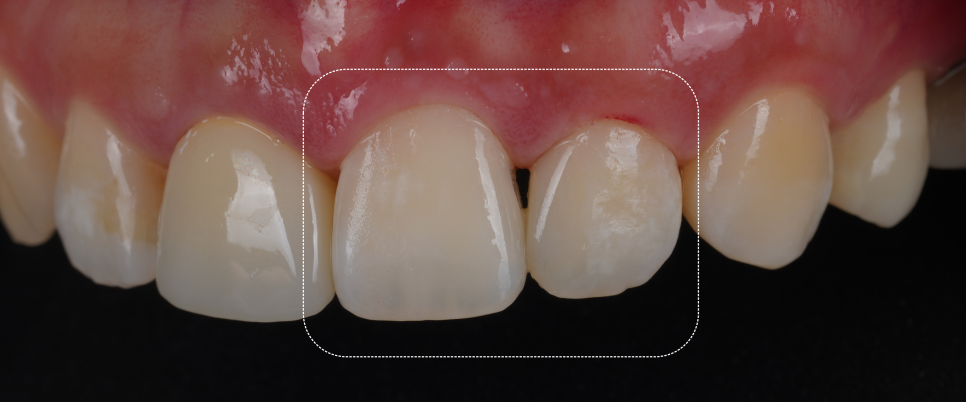

완성 후에는 치아 경계가 사라지고 자연 채광에서 봐도 거친 부분 없이 매끄럽게 보였어요.

이전의 각진 부분도 사라졌죠.

환자분이 거울을 보시면서 “와.. 진짜 감쪽같아요.” 그 한마디로 피로가 다 풀리더라고요ㅎㅎ

치료 후엔 잇몸과 치아 사이에 아주 얇은 ‘블랙트라이앵글’이 남았는데요.

자연스러운 곡선을 살리다 보면 잇몸이 완전히 닿지 않는 부분이 생겨요.

그걸 억지로 메우면 오히려 부자연스러워져요.

자연스러움을 위해 비울 줄도 알아야 합니다ㅎㅎ

광주에서 올라오셨던 환자분이 “멀리 온 보람이 있네요. 너무 마음에 들어요! 원장님~ 저 반대쪽 앞니도 치료할게요!” 치료가 끝나고 이렇게 말씀하시더라고요 ᄒᄒ